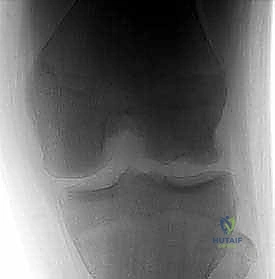

الآفات العظمية الغضروفية في الركبة: دليل شامل لعلاج OCD والنخر اللاوعائي مع الأستاذ الدكتور محمد هطيف في صنعاء

اكتشف كل ما يخص الآفات العظمية الغضروفية في الركبة، التهاب العظم والغضروف السالخ (OCD)، والنخر اللاوعائي (AVN). دليل شامل للتشخيص والعلاج ا…